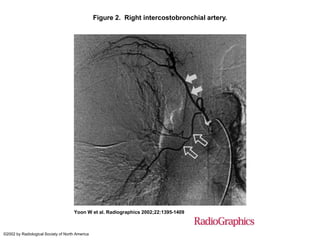

Figure 2. Right intercostobronchial artery.

Yoon W et al. Radiographics 2002;22:1395-1409

©2002 by Radiological Society of North America

Figure 2. Rightintercostobronchial artery. Yoon W et al. Radiographics 2002;22:1395-1409 ©2002 by Radiological Society of North America

• #72 Figure 2.  Right intercostobronchial artery. On a selective right ICBT angiogram, an intercostal branch (solid arrows) and the right bronchial artery (open arrows) are seen to arise from a common trunk.